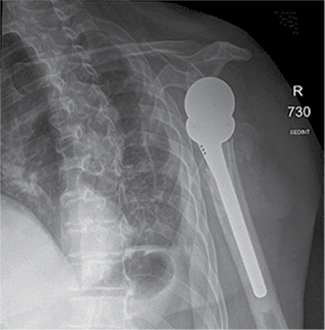

Figure 3. X-ray after shoulder arthroplasty

In a subsequent consultation, it was decided to perform shoulder arthroplasty 11 days later using reverse prosthesis (Delta Xtend, DePuy Synthes) with tuberosity fixation.